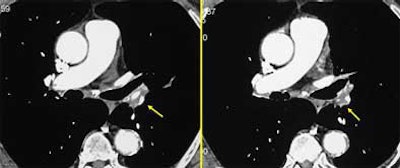

Recanalization: Within the artery, the radiologist can readily detect the recanalization channels, filled with blood that has been opacified by the contrast material. The channels tend to be located very near the areas of nonperfusion due to chronic obstruction, and the presence of focal stenoses can be indicative of recanalization, she said. In addition to transverse sections, additional reformations in the coronal and sagittal planes can often be helpful in delineating the morphology of the channels. "When the stenoses are in the plane of reformation, they are not easily detected in transverse sections," Rémy-Jardin said.

![]() |

| Recanalization of embolic material. |